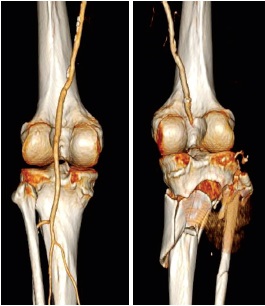

On the 12th day of admission the patient underwent open reduction and internal fixation (ORIF) with dual plate fixation using a two incision technique (Figure 4). After discussion at the multidisciplinary team meating, ORIF was favoured over external fixation as it was deemed that external fixation would not provide adequate ability to reduce the fracture fragments. In addition, the patient already had large fasciotomy wounds and so the advantage of a percutaneous frame had been lost. A plastic surgeon performed skin grafting, harvested from the patient’s thigh, to allow closure of his fasciotomy wounds immediately following ORIF.

Figure 4. Departmental X-rays 14 days after fixation with dual medial and anterolateral plate. Interfragmentary one-third tubular plates with unicortical screws had been used to aid reduction